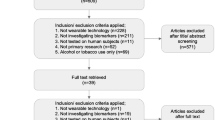

All protocols were approved by the appropriate institutional review board. A Q sensor™ (Affectiva, Waltham, MA) was utilized for all data collection. The sensor is approximately 4 by 5 cm; it is worn on the volar aspect of the wrist and secured by a Velcro band (Fig. 1). The Q sensor continuously records EDA measures in microsiemens (μS), skin temperature in degree Celsius, and acceleration in units g (SI unit of acceleration). Recordings were taken at a sample rate of 8 readings per second. To assess for measurable physiologic changes and to examine the feasibility of technology deployment with data collection in vivo, two separate protocols were used to recruit emergency department (ED) patients and a field subject, respectively, as outlined below.

The University of Massachusetts Institutional Review Board approved the experimental protocol for measurement of biometric profiles of opioid administration in ED patients. Inclusion criteria were (1) age 18–90 years old, (2) chief complaint of acute pain, (3) a clinician’s written order for intravenous opioid analgesic, and (4) ability to provide consent. Exclusion criteria were (1) inability to wear a biosensor, (2) musculoskeletal causes of pain, (3) pregnancy, (4) inability to consent, or (5) upper extremity amputation. Potential subjects were informed that the purpose of the study was to determine the utility of the device to detect opioid use by measuring physiologic change after known exposure. After obtaining informed consent, research staff placed a portable biosensor first on the nondominant wrist unless this interfered with medical treatment (i.e., intravenous lines), then it was placed on the dominant wrist if such interference was identified. EDA, skin temperature, and acceleration were continuously recorded before, during, and 30 min after intravenous opioid administration. Demographic data including age, gender, hand dominance, and history of opioid use, in addition to biosensor responses to drug administration were recorded. Opioid use history was ascertained from patient report, and supplemental prescription history data from the institution’s electronic medical record was included as well.

Field Deployment Protocol: Biometrics of Cocaine Use